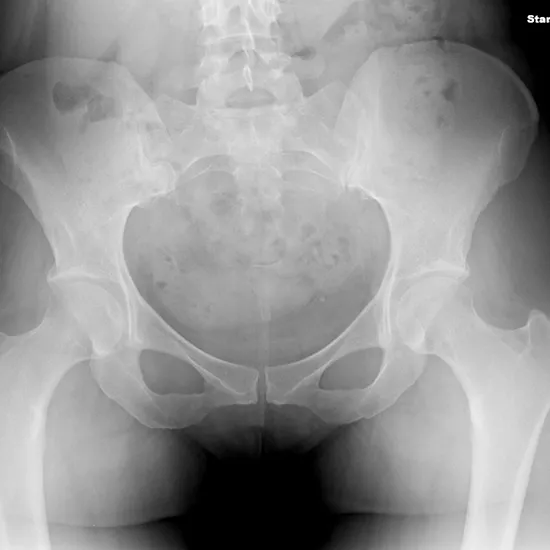

In X-ray Pelvis, the AP and lateral views make it simple to see the hip bones, thigh bones (the top portion of the femur), the hip joint, the skin, and the muscles surrounding the pelvis. AP (anteroposterior) refers to X-rays taken from the front to the back with the legs straight. Lateral refers to the lateral aspect of the flexed pelvis.

Fractures, joint dislocations, inflammations, bone lesions (abnormal alterations), and other degenerative disorders of the pelvis and adjacent tissues may be identified using AP and lateral X-ray views. To diagnose arthritis and hip dislocations.